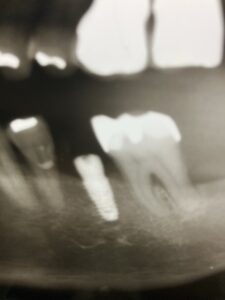

インプラントの上部構造の最終補綴物にメタルボンドと呼ばれるセラミックが使用されていました。今でも使用しますが1番の欠点として破折の可能性があることです。近年、物性や神秘性が格段に向上したジルコニアが、第一選択上がるようになりました。

フルジルコニアクラウンは、歯科補綴の一種で、全てジルコニアというセラミック素材でできた被せ物(クラウン)のことです。従来の金属にセラミックを焼き付けたメタルボンドクラウンとは異なり、アレルギーの原因となりうる金属は使用しません。

- 高い強度と耐久性: ジルコニアは非常に硬く、強い力がかかる奥歯にも適しています。割れたり欠けたりするリスクが低く、長持ちする傾向があります。